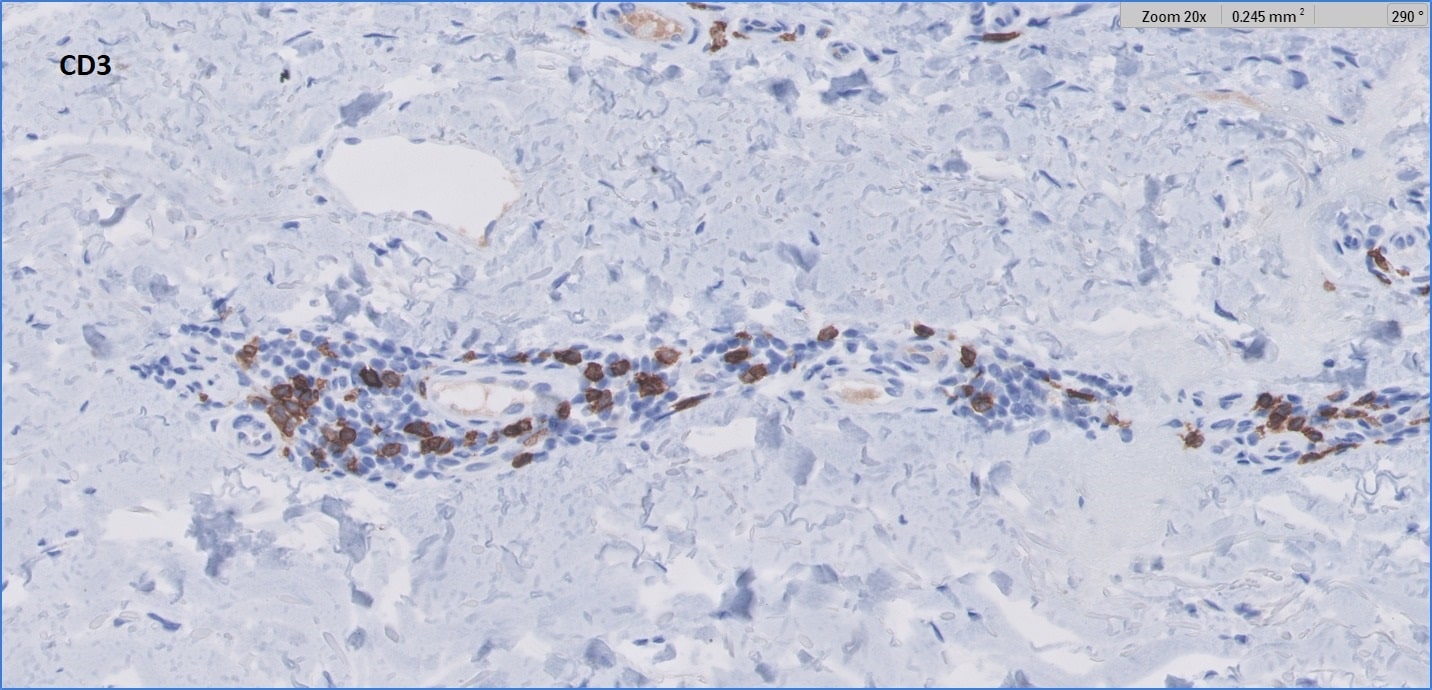

CD3-min